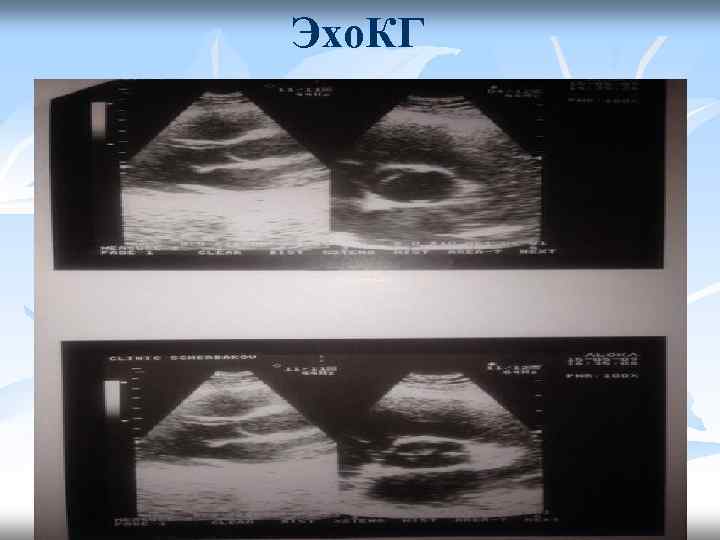

Эхо. КГ

Заключение Эхо. КГ: • Двухстворчатый АК. АР 0 -I ст. МР I ст, ТР I-II ст. ЛР I ст. • Камеры сердца не расширены. Фракция выброса 63%. • Диастолическая функция ЛЖ сохранена. • Перикард без особенностей.